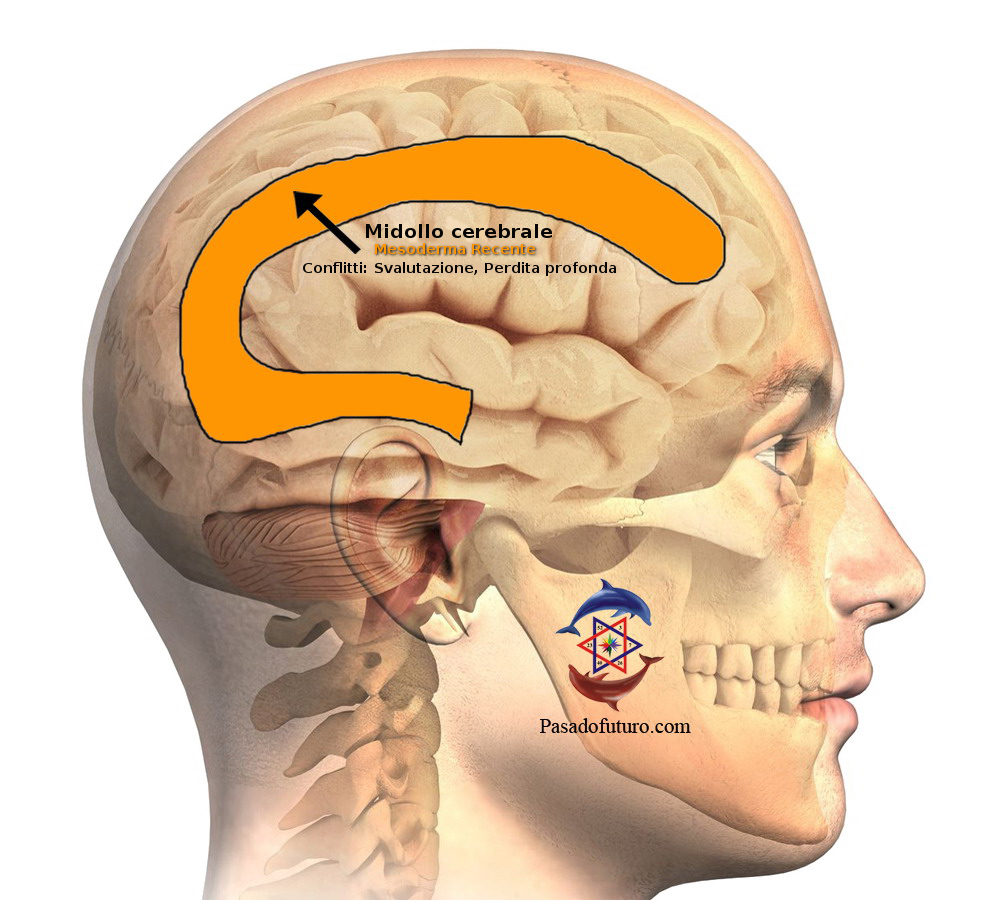

Costellazioni del midollo cerebrale

Si avrà una costellazione del midollo cerebrale, quando la persona ha almeno due SBS (uno in ognuno dei due emisferi nella sostanza bianca) che siano in una qualsiasi delle seguenti condizioni:- Entrambi gli SBS in fase attiva

- Un SBS in fase attiva e l'altro in PCL

- Un SBS in fase attiva e l'altro in crisi epilettoide

- Entrambi gli SBS in fase PCL

- Entrambi gli SBS in crisi epilettoide

La costellazione del Midollo Cerebrale implica un conflitto attivo di svalutazione nei due emisferi cerebrali, ad esempio: le due ginocchia. La lateralità deve essere presa in considerazione.